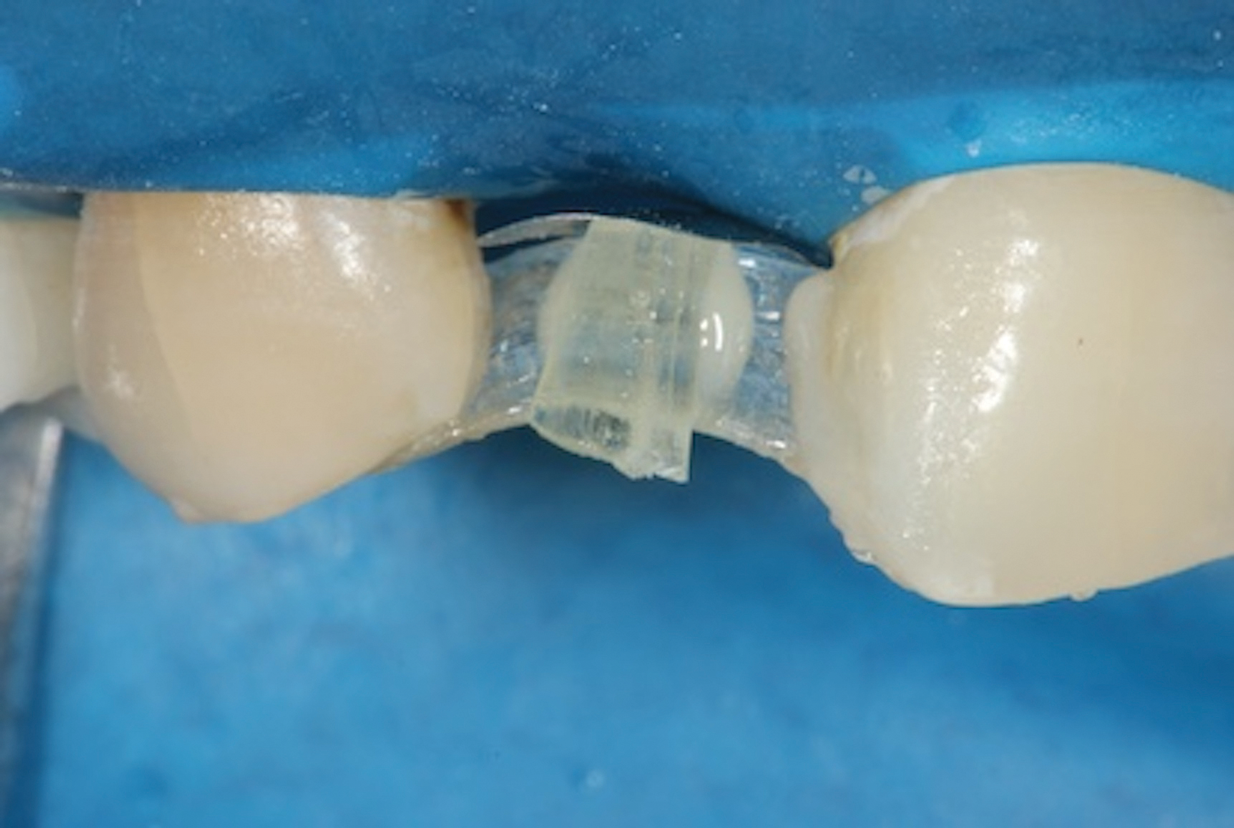

5. Place the Transverse Vertical Fiber

Using a flowable composite, securely bond the smaller piece of fiber vertically to the palatal aspect of the main fiber, ensuring that it is centered and in proper alignment (Figure 8). Position the vertical fiber such that it will be fully embedded within the planned incisogingival dimension of the pontic. It should not be touching the surface of the tissue at its gingival aspect, and care should be taken to avoid exposure of its incisal aspect during fabrication of the pontic. To maximize the structural integrity of the bridge, ensure a robust connection between the vertical and horizontal pieces of fiber.

(8.) Close-up view after placement of the transverse vertical fiber for the pontic. Note how the main horizontal fiber was curved labially to provide space for the reinforcing transverse fiber to be attached to its palatal aspect with flowable composite.

Figure 8